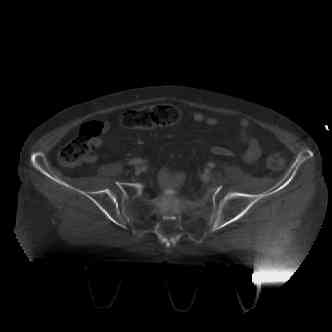

attached are several CT cuts. please let me know if you need more. the CT is pre-pelvic ex-fix placement.

Thank you.

I wouldn't plate the front.

But I would add screws posteriorly.